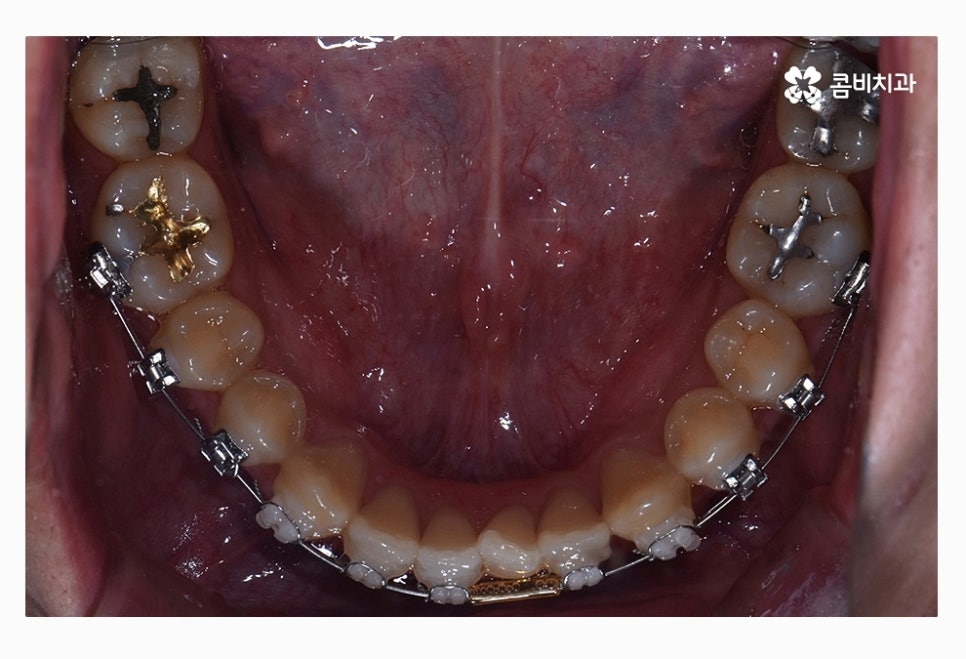

좌측 사진이 윗니이며 우측 사진이 아랫니인데

윗니가 치열이 좀 더 삐뚤다는 것을 알 수 있어요.